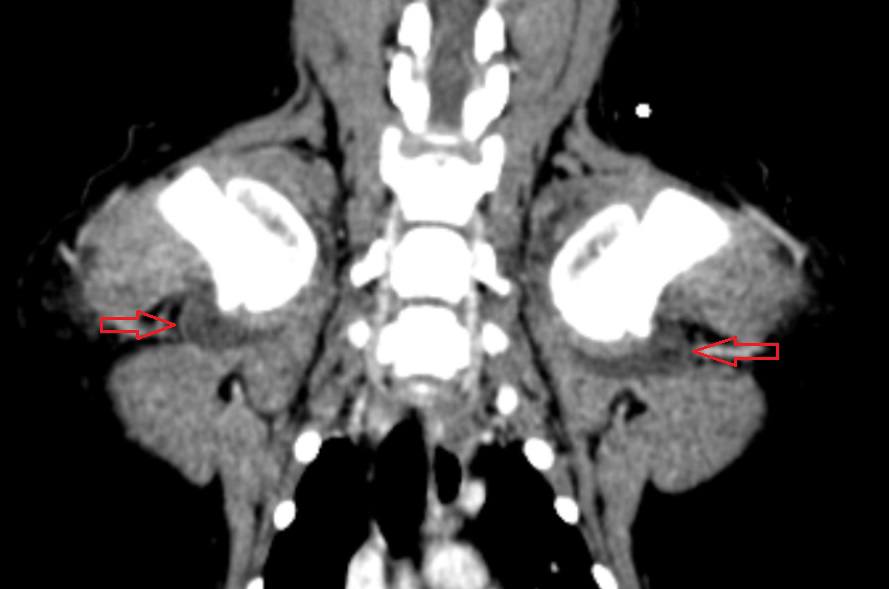

Была проведена повторная КТ с внутривенным контрастированием, по результатам которой было выявлено значительное увеличение размеров капсул в обоих плечевых (рис. 3, 4), локтевых и тазобедренных суставах, а также в левом коленном суставе по сравнению с данными первоначального КТ-исследования.

На основании клинических симптомов, анамнеза приема левофлоксацина, отсутствия ортопедических симптомов до поступления пациента в клинику, результатов анализов крови и синовиальной жидкости, а также проведенной КТ был поставлен диагноз «множественная артропатия, вызванная применением фторхинолонов».